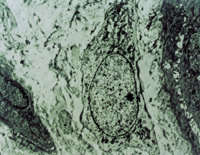

經(jīng)MEBT/MEBO治療5天,可見創(chuàng)面纖維細(xì)胞,成纖維細(xì)胞生長(zhǎng)比較活躍(圖5-3-13)。

5-3-13 MEBT/MEBO治療5天,成纖維細(xì)胞生長(zhǎng)活躍  TEM×2000